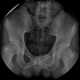

Melorheostosis with osteopoikilosis

Melorheostosis is a medical developmental disorder and mesenchymal dysplasia in which the bony cortex widens and becomes hyperdense in a sclerotomal distribution. The condition begins in childhood and is characterized by thickening of the bones. [Source: Wikipedia ]